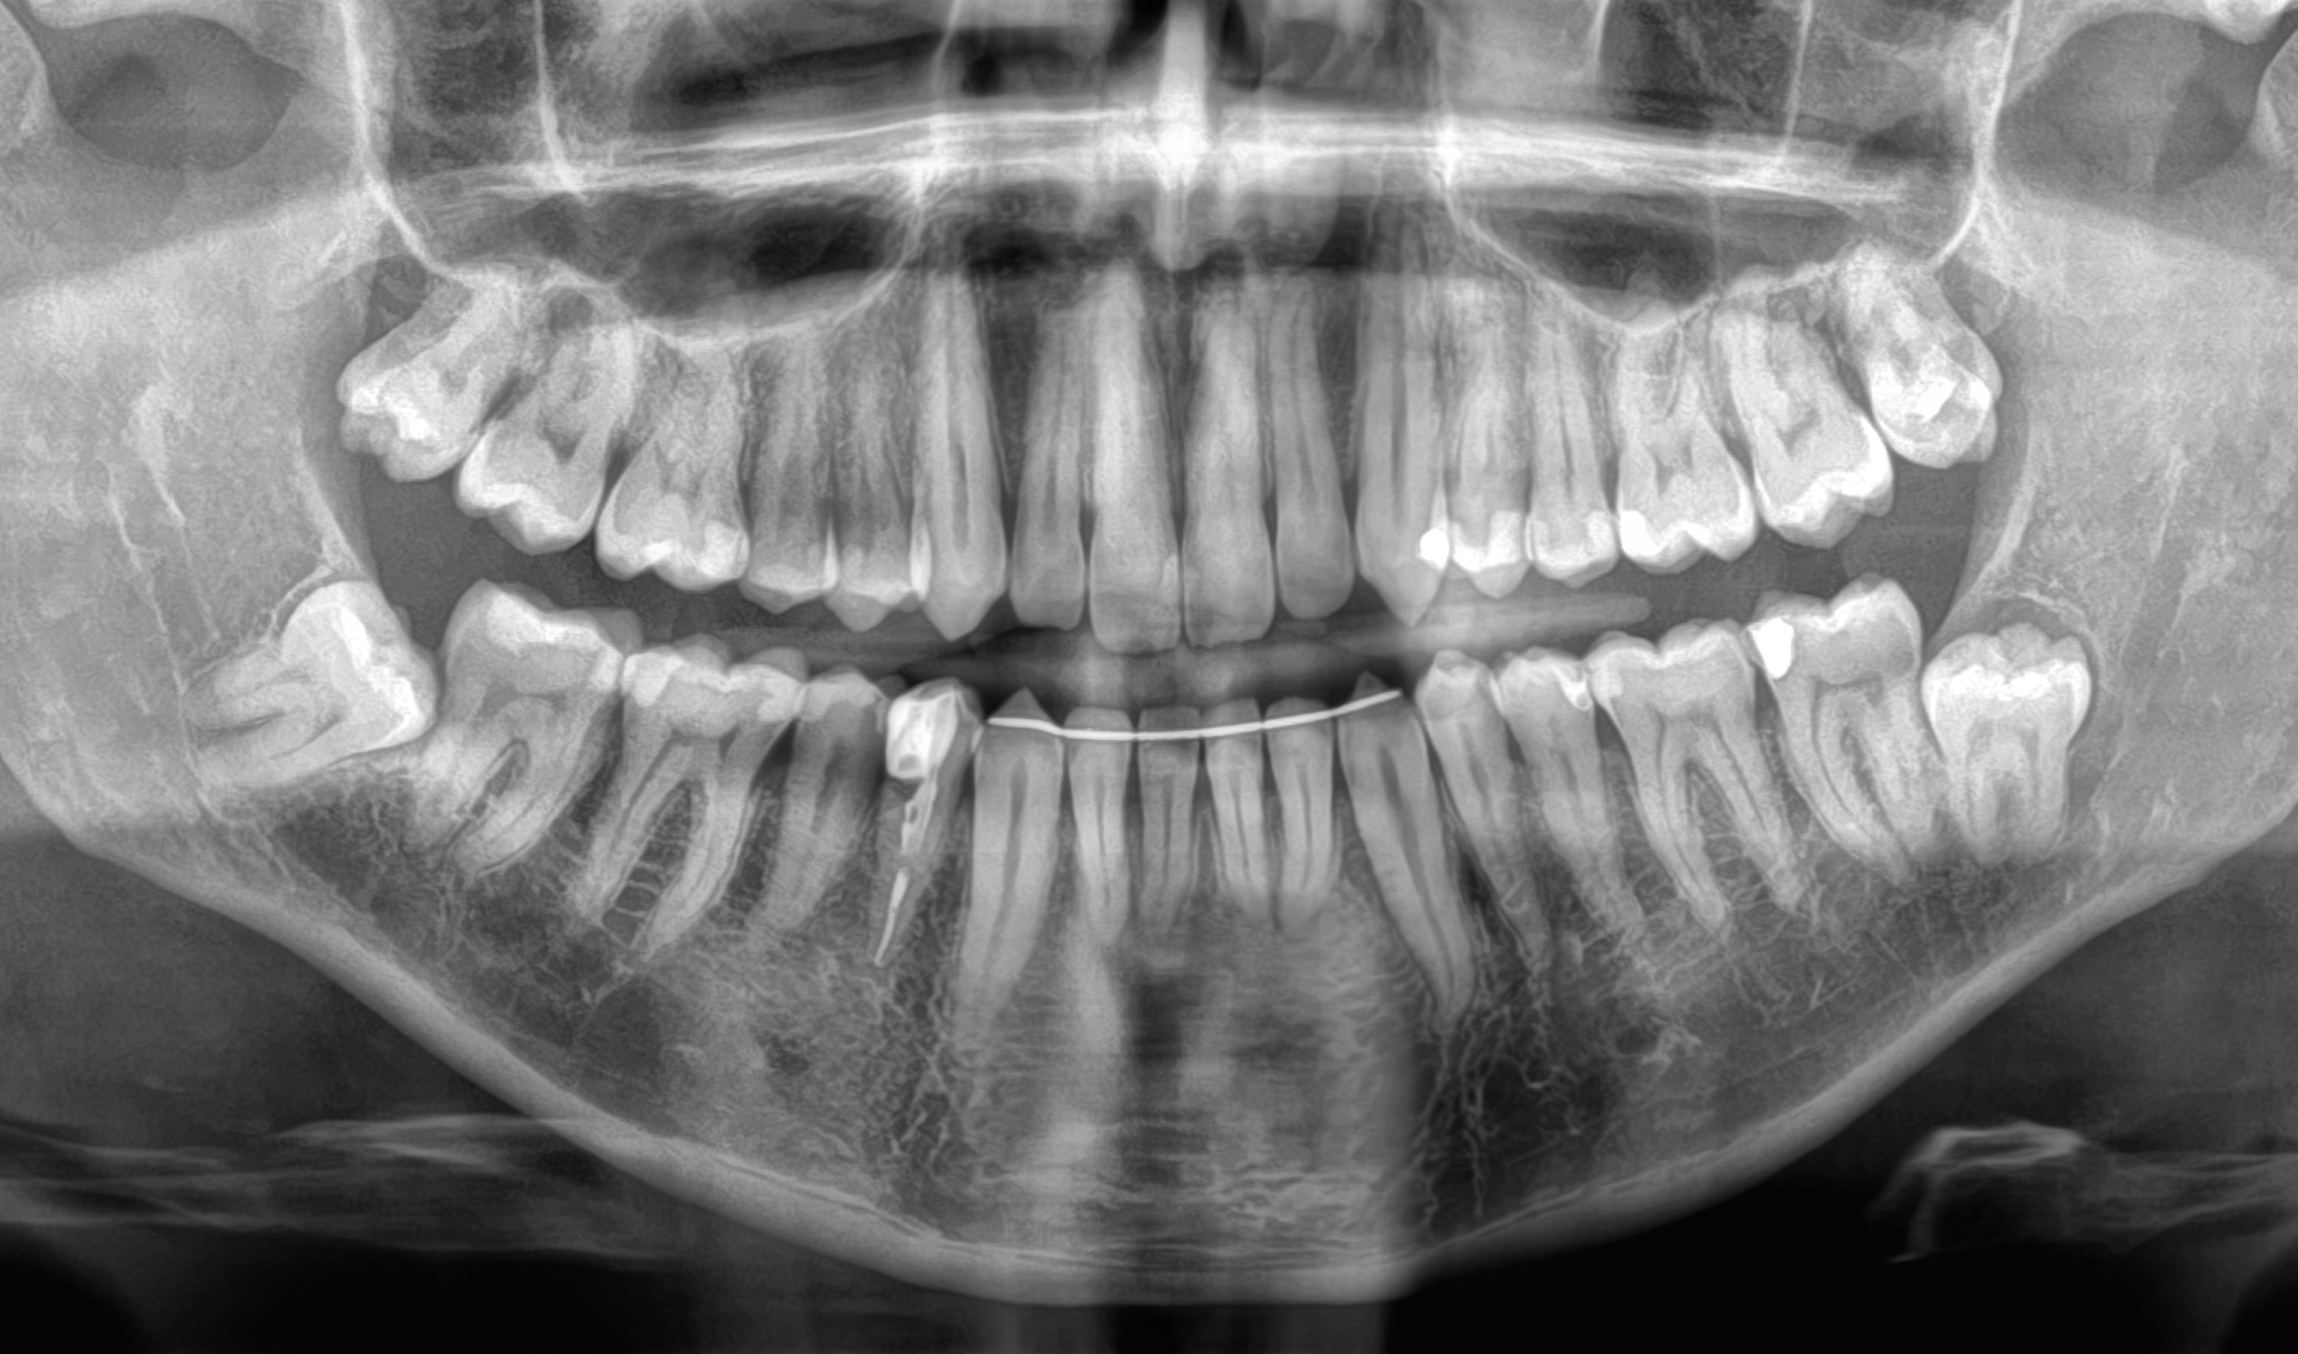

CASO 1

Estrazione di tutti e 4 i denti del giudizio per disodontiasi. Operazione chirurgica avvenuta in due sedute.